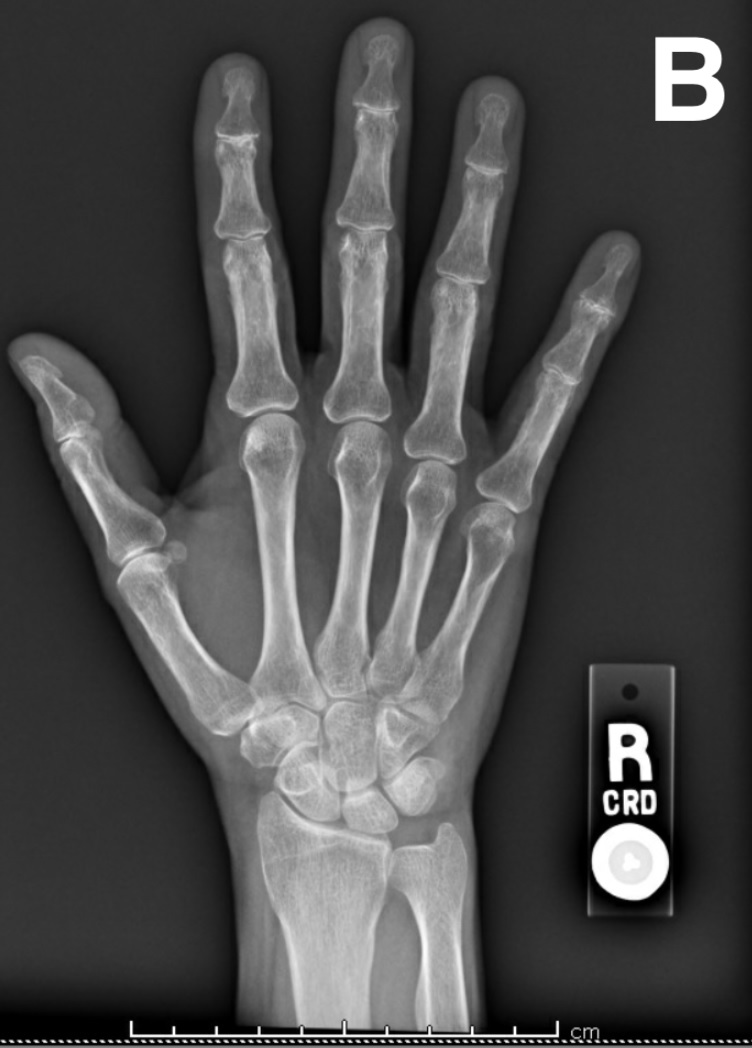

Distal interphalangeal joint osteoarthritis (Heberden nodes) Image Distal Interphalangeal Joint Erosion Diagnosis is made radiographically with. Eventually, patients with erosive hand oa will develop deformities of the distal interphalangeal (dip) and proximal interphalangeal (pip) joints, medial and lateral subluxations, as well as instability, flexion deformity and ankylosis. The instability and ankylosis of the interphalangeal joints result in a rapid progressive loss of. It can develop in the hinge joints of the. Distal Interphalangeal Joint Erosion.

A Woman With Worsening Hand Pain and Stiffness Consultant360 Distal Interphalangeal Joint Erosion Diagnosis is made radiographically with. The dominant features are those of osteoarthritis, particularly in terms of distribution: It can develop in the hinge joints of the fingers and less frequently in the toes. Erosive osteoarthritis has a predilection for the hands. Osteoarthritis occurs with the highest prevalence in the distal interphalangeal joint of the hand and has been divided into. Distal Interphalangeal Joint Erosion.